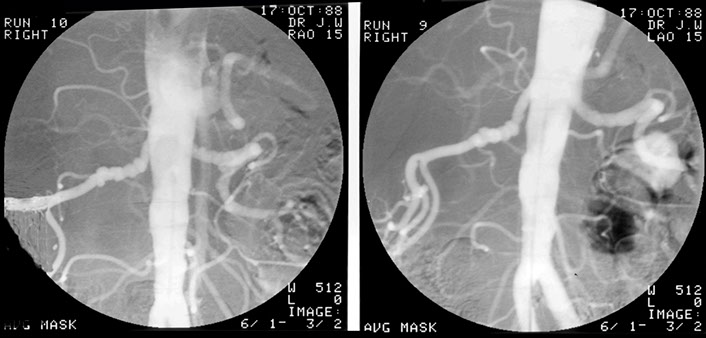

This patient developed several strictures two years apart. This one is a popliteal stricture.

Popliteal stricture post dilatation

And this represents the second stricture two years later in the left lower femoral artery

And this is the post-dilatation image of the femoral stricture.